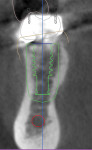

A CBCT image (Figure 2) and digital impression (Figure 3) were obtained for diagnosis and treatment planning. To facilitate this, the CBCT image and impression were merged into the implant planning software for evaluation. Tooth No. 30 was removed from the virtual model, and a virtual restoration was created (Figure 4). Next, the vital structures and osseous anatomy were identified, and a virtual implant was planned (Figure 5 and Figure 6). A virtual fully guided surgical template was created (Figure 7) and then sent to the in-office printer for guide fabrication (Figure 8 and Figure 9). Using a flapless technique, the crown of tooth No. 30 was removed, and the necrotic roots were sectioned and surgically removed (Figure 10 and Figure 11). Following this, the CT template was placed, the osteotomies were completed, and the implant was placed in a guided fashion with 60 Ncm of torque (Figure 12 and Figure 13). After the osseous socket was grafted with allogenic bone, a healing abutment was placed, and the tissue was stabilized without mobilization using 3-0 chromic sutures (Figure 14 and Figure 15). An immediate post-operative CBCT scan was used to verify that the implant was placed as planned (Figure 16 and Figure 17).